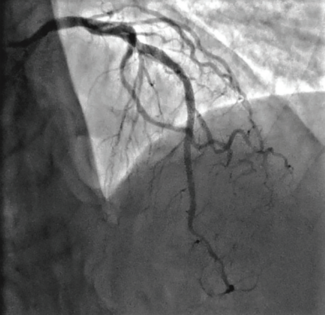

We have been using IVL in the coronary arteries since its approval last year and have had a very pleasant experience. IVL’s ability to change the compliance of calcified lesions has been very helpful.